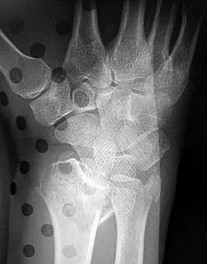

A 22-year-old male falls onto an outstretched hand and sustains a displaced fracture through the proximal pole of the scaphoid. Avascular necrosis of the proximal pole is highly likely due to the disruption of its primary vascular supply. Which vessel provides this critical retrograde perfusion?

Explanation

The primary blood supply to the scaphoid is from the dorsal carpal branch of the radial artery, which enters the dorsal ridge of the scaphoid at the waist and courses proximally. This retrograde blood flow makes proximal pole fractures highly susceptible to avascular necrosis and nonunion. The superficial palmar branch provides a minor supply (about 20%) to the distal pole.